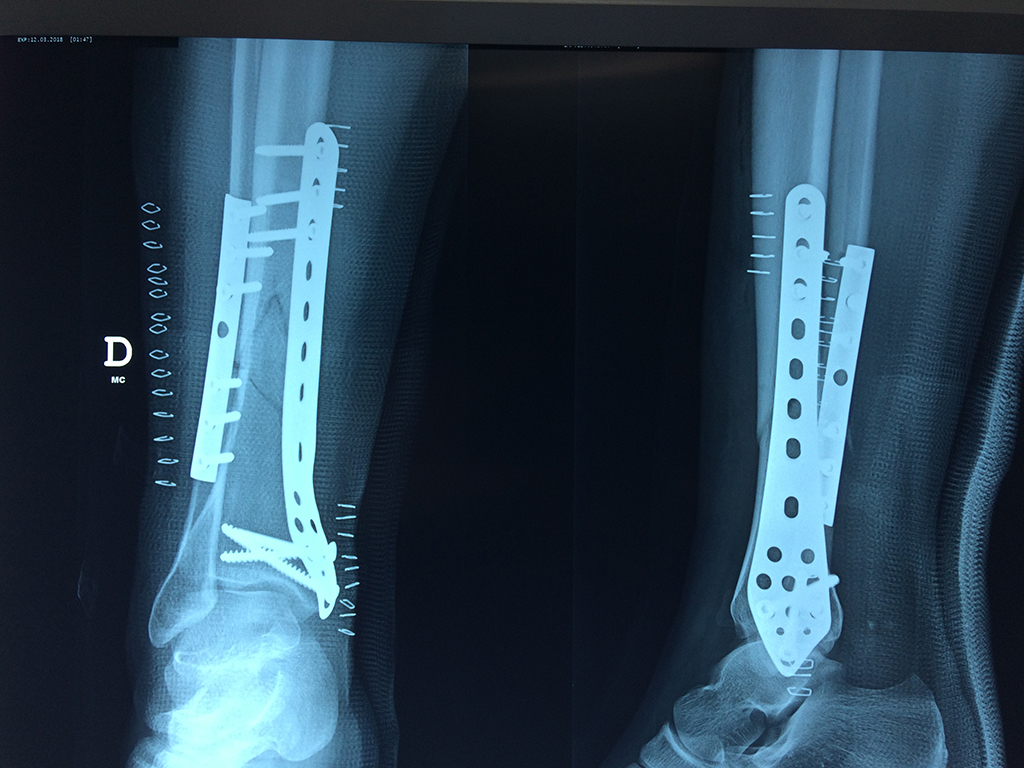

Cirugias en El Salvador - Perone y Tibia

Aunque cada uno de estos huesos puede fracturarse por separado, normalmente la rotura es una lesión que se produce de forma conjunta

La mayor parte de las roturas implican a la parte proximal del hueso (parte del hueso próximo a la rodilla) o a la parte distal (parte del hueso cerca del tobillo).

Debido a la fina cobertura de piel que recubre la tibia y el peroné, las fracturas generalmente son abiertas, es decir, el hueso roto rasga la piel, atravesándola. Las fracturas de tibia y peroné generalmente se producen por un fuerte impacto o torsión.